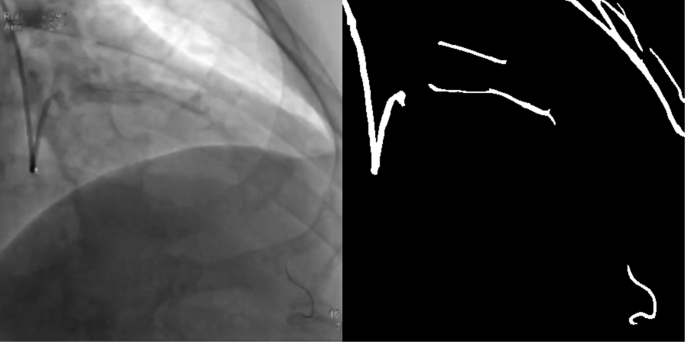

In our work, we choose two parts of the dataset for training, one is the public DRIVE [28] dataset which is widely used for vessel detection, and the other dataset comes from the angiography video of coronary interventional surgery. 170 video clips contain clear blood vessels with contrast agents were annotated manually by medical students. We record hundreds of videos of interventional surgeries, clip the videos which have contrast agents, then do interframe sampling about every three frames, finally we get 4904 annotated angiography images, as shown in Fig. 4. The annotated images are divided into two sets by selecting 4354 images for the train set and 550 images for the validation set during the training.

As shown in Fig. 8, two situations can cause segmentation results to fail. First, there are some tissue structures in the video image which have close grayscale value and similar shape with the angiographic vessels, which will cause the tissue to be segmented together. The second is that when the contrast agent is very thin or uneven, the coronary blood vessels will not be segmented. Considering these two situations, we need to make the dataset bigger. At the same time, we need also to consider the differences between the imaging effects of different contrast devices. The time-consuming of this method is about 59ms per frame on a GeForce GTX 1070 GPU, it is almost real-time if the rate set by the coronary angiography system is 15f/s. The algorithm still has room for continuous optimization and will continue to be improved in the future.